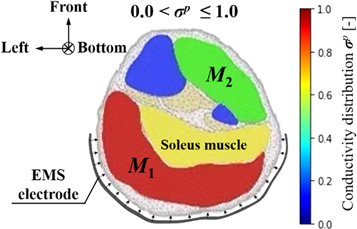

In order to quantify the response muscle areas of human calf muscles under EMS, the conductivity distribution images reconstructed by fd-EIT were analyzed by a dedicated Python script. Figure 5 shows an example of σ p of human calf muscles in the range of 0 < σ p ≤ 1.0 and the mesh structure used in this study. The mesh consists of 3053 trihedral element and 5263 points. In this paper, the view direction of σ p is from the top to the bottom of the human leg, which is contrary to the direction of typical CT images. Normally, the σ p indicates two response areas affected by EMS, which are denoted as M1 and M2 response areas. The conductivity values of M1 and M2 were changed in the pre-training, post-training, and relaxation parts. According to a typical MRI image of the calf muscle structure, M1 and M2 were calculated based on J by using the dedicated Python script in each subject. The reason why σ pre shows high conductivity in M1 and M2 before EMS is that the each subject's muscles have their own conductivity under the modeled inhomogeneous conductivity distribution in the forward problem. Therefore, σ pre was used as the baseline for each experimental subject in this study. The conductivity difference ratios Δ σ post– pre between pre- and post-training parts and Δ σ relax– pre between pre-training and relaxation parts are defined as

Figure 5. Example of conductivity distribution images σ p of human calf muscles.